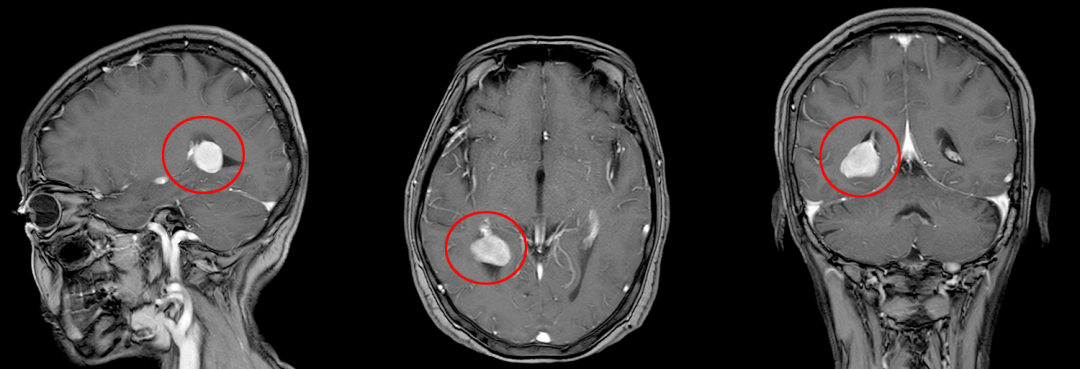

▲患者头颅MR增强

考虑脑膜瘤可能!

入院后,神经外科主任王文华立刻组织术前讨论并表示:该患者肿瘤位于三角区,位置较深,肿瘤大小2.2cm*1.6cm,肿瘤周围血管、神经丰富,手术难度较大,传统开颅肿瘤切除术中出血多,肿瘤定位困难,对血管神经的破坏较大。市中医医院引进的术中导航系统可以精准定位肿瘤,计算最优路径,减少脑组织的损伤,减少术中出血。

▲术中神经导航模拟肿瘤位置,精准定位,计算最优路径

经神经导航的辅助,选取微创小切口,完整切除肿瘤,术中出血少,对功能区保护满意。